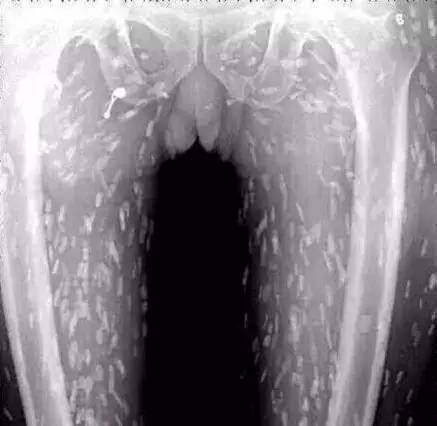

湖南一位孩子住院后,發現肺部有很大的陰影。原來,由于經常吃不熟的食物,他的肺里長滿寄生蟲,已經被「蟲子」吃出了兩個洞▼